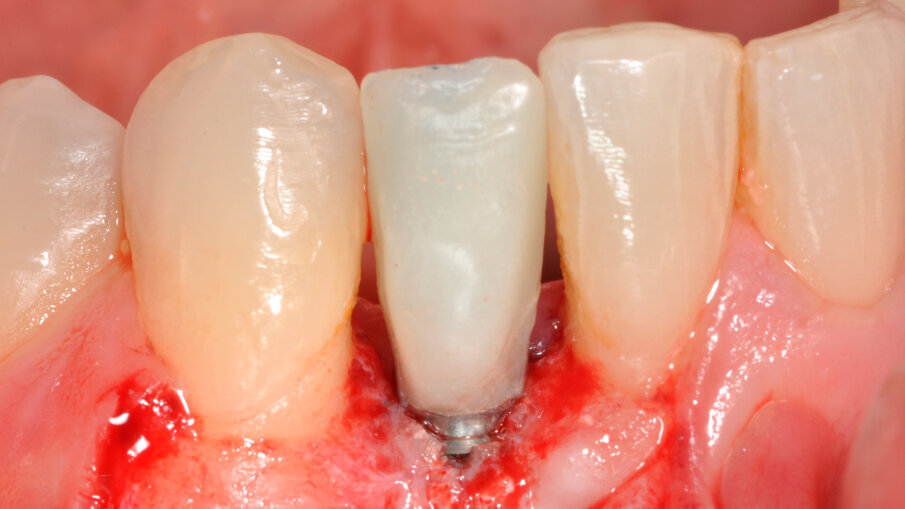

Zavedení implantátu

V rámci prvního kroku zavádění implantátu byly pomocí chirurgické šablony vyhodnoceny biologické aspekty podle pravidla 3A-2B (obr. 3). První pozice pro vrtání byla vyznačena tak, aby bylo dosaženo 2B a zajištěn úhel osteotomie pomocí vrtáku Precision Drill EV (Dentsply Sirona). Úhel byl potvrzen a osteotomie v hloubce pro implantát byla preparována pomocí vrtáku Twist Drill EV (Dentsply Sirona; obr. 4). Hloubka osteotomie byla zkontrolována pomocí nástroje Implant Depth Gauge EV (Dentsply Sirona (obr. 5). Poté byl zaveden implantát OsseoSpeed EV 3.6 o délce 11 mm (obr. 6). Předpokladem bylo, že zbývající aproximální kost poskytne oporu aproximální papile. Periapikální RTG snímek pořízený bezprostředně po zavedení implantátu potvrdil, že implantát není v kontaktu s žádným ze sousedních kořenů (obr. 7). Poté byl za použití otiskovací kapny Implant Pick-up Design EV (Dentsply Sirona), což je samonaváděcí otiskovací komponenta, která se umisťuje do implantátu, pořízen otisk, jehož účelem bylo získání informací o pozici implantátu (obr. 8). Provizorní abutment Temporary Abutment EV byl upraven v oblasti krčku tak, aby se zabránilo kontaktu s aproximální kostí a bylo možné správné dosednutí (obr. 9). Za použití kofferdamu pak byla pryskyřicí ihned upevněna provizorní náhrada (obr. 10). Poté byla náhrada sejmuta, dokončena, vyleštěna a za lehkého přitlačení opět nasazena.

Definitivní náhrada

Pacient byl objednán na kontrolu týden po chirurgickém zákroku. V té době bylo dosednutí provizorní náhrady shledáno uspokojivým (obr. 11). Obrázek 12 zachycuje digitální plánování abutmentu Atlantis Crown Abutment ze zirkonu s adekvátním prostorem pro vrstvy keramiky. Definitivní náhrada byla vyrobena v zubní laboratoři s ohledem na dosažení harmonie se sousedními zuby (obr. 13). Byl také vytvořen prostor pro aproximální papilu. Abutment kotvený šroubkem s lingválním přístupem lze vidět na obrázku 14. Provizorní náhrada byla vyměněna za definitivní (obr. 15). Subgingivální část abutmentu poskytla oporu měkkým tkáním a byl zajištěn prostor pro mezizubní papilu. Atlantis Crown Abutment byl dotažen točivým momentem 25 Ncm (obr. 16). Lingvální přístup ke šroubku byl nejprve zakryt výplňovým materiálem (PTFE) a poté kompozitem. Následně byl pořízen další RTG snímek implantátu s upevněným definitivním abutmentem Atlantis Crown Abutment (obr. 17). Na obrázku 18 lze vidět konečný výsledek s definitivní náhradou, na němž je patrný adekvátní obrys měkkých tkání a vyplnění aproximálního prostoru. Keramika rovněž dokonale napodobila odstín sousedních zubů.